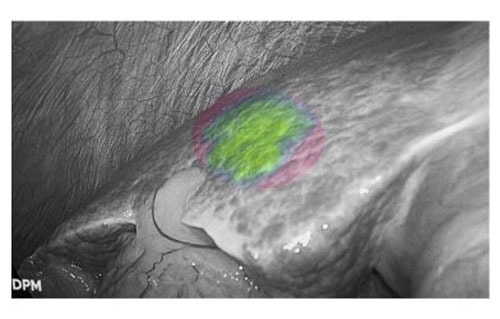

由于肝癌细胞对吲哚菁绿(ICG)代谢情况受损,因此通过荧光显影技术,病变细胞能够清晰呈现。这一特性不仅实现了肿瘤的精准定位,更使肿瘤边界清晰可见,帮助医生快速识别安全手术切缘,精准规划切除范围,在确保肿瘤完整切除的同时,最大限度保留健康肝组织。同时,避免误伤周围重要血管,显著提高了手术安全性,改善了患者的短期疗效和长期预后。

患者肝右后叶肝癌,根据三维重建精准阻断右后肝蒂,获得缺血线后进行荧光反染,显示肝脏切面的荧光和非荧光界面,助力解剖性肝右后区切除。

三维重建技术直观呈现肝段划分及血管、胆管解剖关系,而荧光显影技术则通过肝段染色,全程显露段间静脉,有助于识别肝内肝段间的界限,使肝胆外科医师可以全程实时观察肝脏切面变化,及时作出调整,优化手术方案,实现真正意义上的解剖性精准治疗。此外,吲哚菁绿(ICG)经胆道排泄的特性使术中胆管结构呈现清晰绿色荧光,大幅提升胆总管辨识度,有效降低腹腔镜手术中胆管损伤风险,为复杂肝胆手术安全性再添保障,显著降低了胆管损伤及相关并发症的发生率,进一步提升了手术安全性。